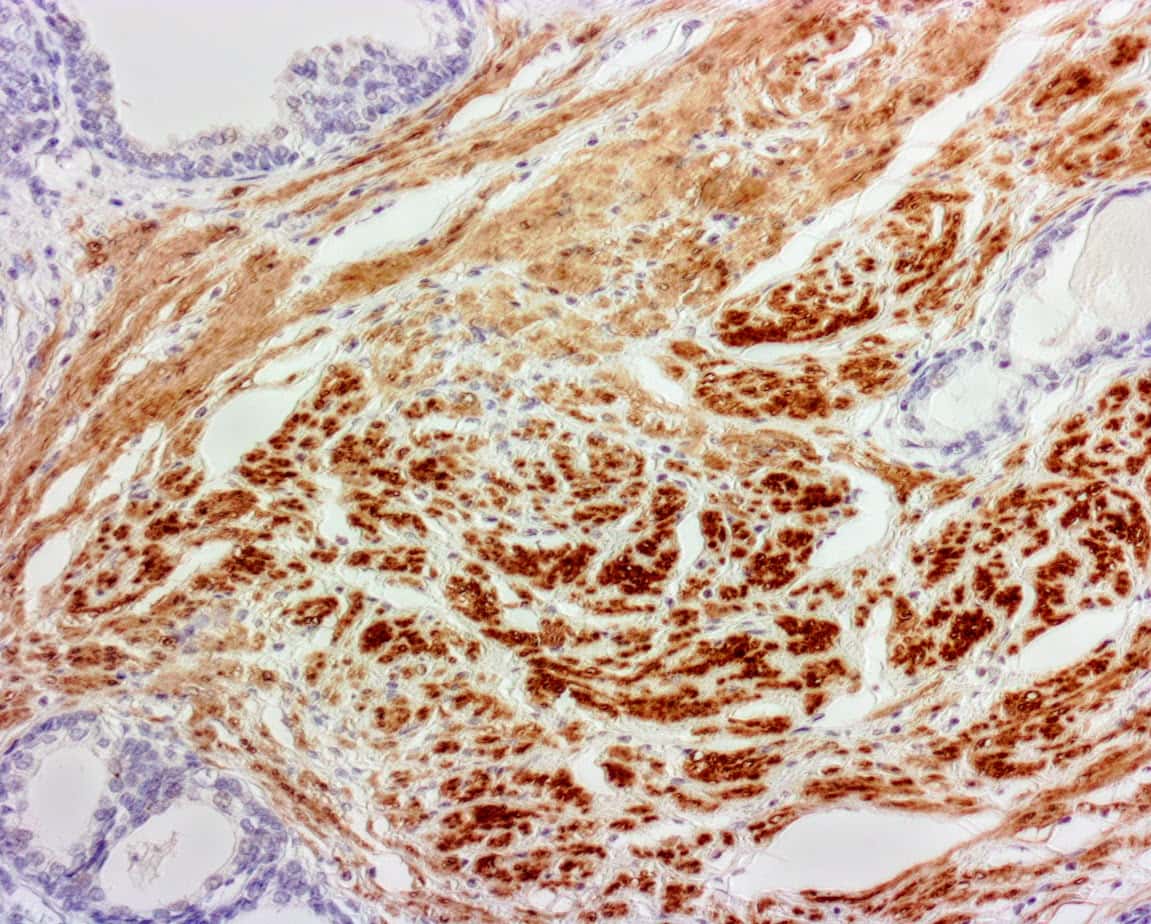

ihcDirectĀ® Calponin is a polymerized horseradish peroxidase (pHRP) labeled anti-calponin antibody (Clone C126) intended for laboratory use to qualitatively identify by light microscopy the presence of calponin in contractile smooth muscle and myoepithelial cells in sections of formalin-fixed, paraffin-embedded (FFPE) tissue or frozen tissue sections using immunohistochemistry (IHC) test method. The clinical interpretation of any staining or its absence should be complemented by morphological studies using proper controls and should be evaluated within the context of the patientās clinical history and other diagnostic tests and proper controls interpreted by a qualified pathologist and/or physician. This conjugate has been pre-diluted and optimized for IHC use without further dilution.

ihcDirectĀ® Calponin Kit (Clone C126) immunohistochemistry (IHC) reagent is for use on frozen and formalin-fixed-paraffin-embedded tissues. Antibody (Clone C126) reacts with calponin, which is a 34kD polypeptide that interacts with actin, tropomyosin, and calmodulin. Calponin is involved in smooth muscle contraction mechanisms and is expressed in smooth muscle tissue. It is also observed in myoepithelial cells. The calponin antibody may be used as a marker of the differentiated contractile phenotype of developing smooth muscle and to help differentiate benign sclerosing lesions of the breast from carcinoma. The ihc Blocker provided in the kit used prior to applying pHRP Calponin conjugate can reduce background and nonspecific staining. Chromogen 3,3ādiaminobenzidine (DAB) is used in this kit.